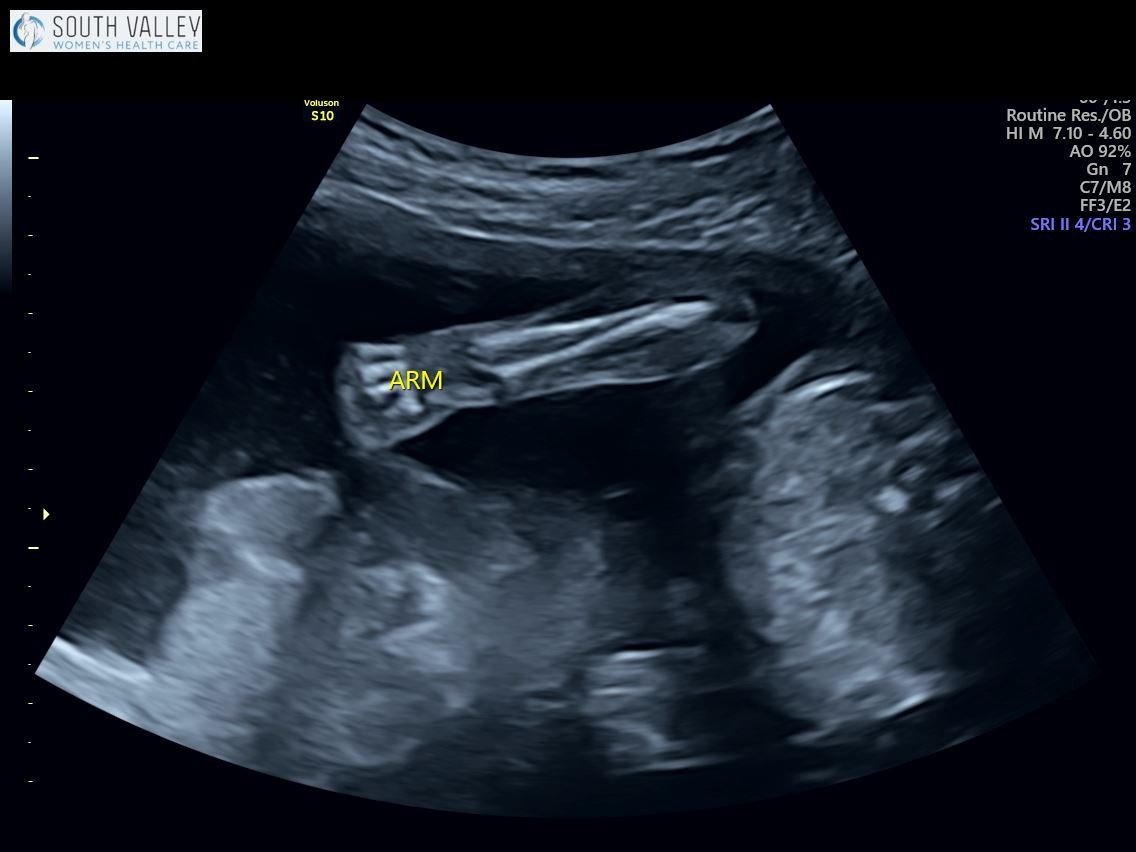

Yesterday we had our anatomy scan and it went well! Everything is looking perfect so far — the brain, the heart, all of those internal organs are in the right place and best of all, I got to see some of he sweetest shots of his cute little face! If you’ve ever wondered what a 19 week old baby in pregnancy looks like, here you have it. She said it’s rare that she gets a face shot this good at such an early age so I was pretty happy about that!

19 Week Ultrasound